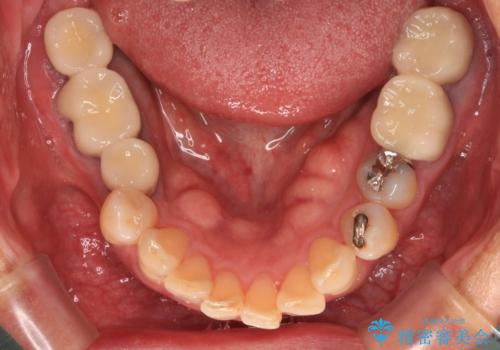

通常、奥歯を抜歯した状態で長年放置すると、咬み合う歯が伸びてきて、咬み合わせが乱れてしまうことが多いです。そのような場合には、部分的な矯正治療などが必要となるのですが、こちらの患者様は幸運なことに咬み合わせが乱れていなかったため、インプラント埋入から速やかに補綴治療を行うことができました。